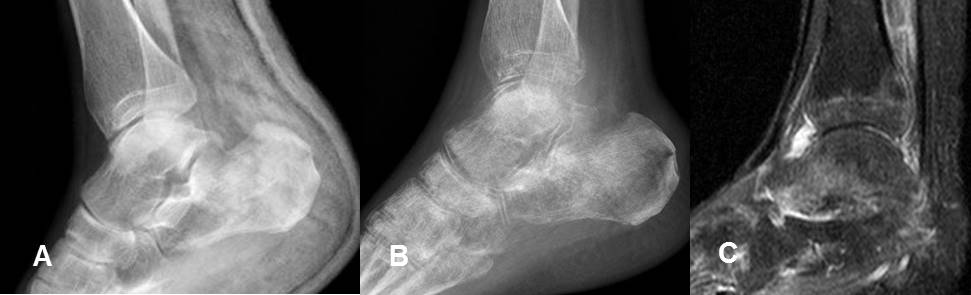

Fig 125. Seudoartrosis.

A: Rx AP y B: TAC reconstrucción sagital. Fractura con extremos escleróticos y con poca formación de callo óseo, por seudoartrosis.